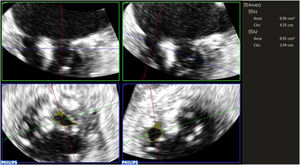

MÉTODOSSe realizó un registro prospectivo de un total de 167 pacientes consecutivos en los que se llevó a cabo una reparación valvular mitral percutánea de borde a borde en nuestro centro desde octubre de 2010 a mayo de 2023. La ecocardiografía transesofágica del procedimiento se llevó a cabo utilizando una plataforma Philips Epic 7 y una sonda X7-2t (Philips Medical Systems, Estados Unidos). Todas las mediciones se realizaron de acuerdo con las guías de práctica clínica1,4,8. Inmediatamente antes del inicio del procedimiento y después de la liberación del último clip, en la propia sala de hemodinámica, mediante ecocardiografía transesofágica, se utilizó el Doppler continuo para la evaluación del gradiente medio a través de la válvula mitral y del AVM por THP9. El haz del Doppler continuo se colocó en el centro del orificio más grande para obtener un espectro Doppler de buena calidad. Tanto para los gradientes como para el THP se realizó el promedio de 3 latidos, y de 5 latidos en pacientes en fibrilación auricular. En los casos en los que el flujo transmitral presentaba dos pendientes, una inicial más abrupta y otra más tardía y tendida, se usó el segmento mesodiastólico para el cálculo del THP, como recomiendan las guías de práctica clínica1,4,8. Además, se realizaron adquisiciones de zoom 3D de la válvula mitral para la medición AVM por planimetría 3D mediante el software de cuantificación 3D (3DQ), de Philips Medical Systems (figura 1). La válvula mitral se muestra utilizando tres planos orientados ortogonalmente. Para no sobreestimar el AVM, el plano en el que se hace la medición se orienta perpendicularmente a las valvas de la válvula10,11. Después del clipado se realizó la medición del área 3D de cada orificio por separado, ya que en la mayoría de los casos los orificios tienen una orientación diferente en el espacio (figura 1), sumando finalmente el área de ambos como AVM total. El comité ético de investigación del hospital aprobó el estudio.

En lo que respecta a la medición del AVM posclip, se obtuvo un AVM promedio por suma de orificios por planimetría 3D de 2,87 cm2, con una reducción cercana al 50% respecto al AVM medida previamente a la intervención por este método. En cuanto al AVM medida por THP, el promedio fue de 1,89 cm2, mientras que el gradiente medio transvalvular fue en promedio de 3mmHg (DE±1,19). La resolución temporal promedia de las adquisiciones zoom 3D fue de 16 volúmenes/s (Hz) (rango entre 12 y 20). El AVM obtenida mediante planimetría 3D presentó una mejor correlación con el gradiente medio posclip (y=3,3351 + −0,2176 x, r=0,46, p<0,001) que el AVM obtenida por THP (y=2,1937 + −0,08978 x, r=0,19, p=0,048) (figura 2), aunque, como puede observarse en la figura, existió una gran dispersión de puntos y la correlación fue pobre (r=0,46 para la planimetría 3D y r=0,19 para el THP). La planimetría 3D obtuvo además una mayor concordancia interobservador (coeficiente de correlación intraclase de 0,90 y coeficiente de variación del 9,6%) que la conseguida por THP (coeficiente de correlación intraclase de 0,81 y coeficiente de variación del 19,7%).